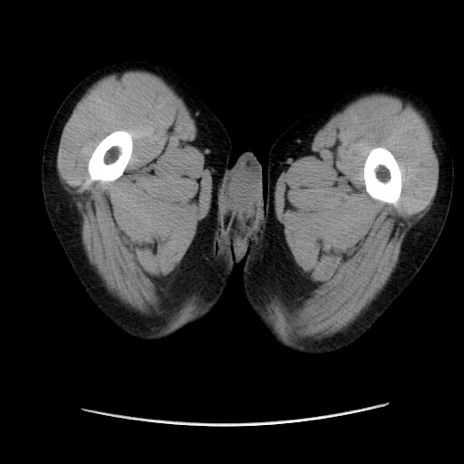

症例37(横断像)

【症例】40歳代 男性

【主訴】腹痛

【現病歴】4時間ほど前に電車に乗車中に臍部上より腹痛出現。徐々に増悪し起立困難となり、救急外来受診。生ものは数日食べていない。今朝お雑煮を食べた。

【身体所見】BT 36.8℃、BP 117/84mmHg、HR 91/min、SpO2 97%、苦悶様、腹部:臍上部広範囲圧痛あり、反跳痛±

【データ】WBC 8100、CRP 0.03